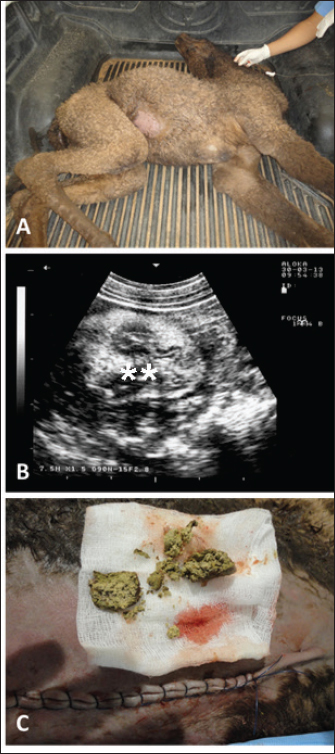

Full details including presenting complaints, symptoms, diagnosis, treatment, and outcome of the 25 dromedary camels with depraved appetites are listed in Table 1. The dromedary camels with depraved appetites had different presentations, but all of the examined animals had a history of eating foreign or inanimate objects. Pica was evident in some cases upon initial clinical examination (Fig. 1). Twelve of the camels (48%) were admitted with a history of loss of body weight and 8 (32%) with partial or complete loss of defection. Seven out of the nine (77.8%) lactating camels in this study suffered from decreased milk production. An example of such a case is shown in Figure 2. In animals undergoing laparotomy, the foreign bodies were surgically removed as shown in Figure 3. Bouts of repeated vomiting were also found in 5 (20%) of the camels. In animals that underwent rumenotomy, the foreign bodies were removed as in Figure 4. Eating feces (coprophagia) was also found in six camels as shown in Figure 5. Sixteen (64%) of the camels were recovered while the remaining 9 (36%) did not survive.

Fig. 2. Ultrasonographic findings in an adult female camel with a history of pica. The animal was admitted with a 7-day history of decreased fecal output and abdominal distension (A). Image (B) shows an obstructing foreign body occluding the small intestines partially (stars) using a 3.5 MHz sector transducer.

Fig. 3. Ultrasonographic findings in a 30-day camel calf with a history of pica. The calf was admitted with a 5-day history of no defection and abdominal distension (A). Image (B) shows an obstructing enterolith occluding the small intestines (stars) using a 7.5 MHz sector transducer. Image (C) shows the obstructing enterolith detected at right-sided surgical laparotomy.

Sonographic and postmortem findings are summarized in Table 2. In cases of camels presented with a history of pica and with decreased or total absence of feces, the obstructing foreign body was imaged in 10 of the 25 camels (40%) occluding completely or partially the intestines that may be confirmed at abdominal surgery (Figs. 2, 3, and 6). Foreign bodies within the rumen could not be visualized with ultrasound owing to the gas content. In cases where the rumen is impacted by sand, small pin-points revealing acoustic enhancement were imaged in 5 (20%) of the camels. An example of these cases is shown in Figure 7. Foreign bodies were removed from the rumen or intestines at exploratory rumenotomy and laparotomy, which included plastics, cloths, sand, mud, robes, wool balls, glasses, or even metallic objects that were blunt or sharp (Figs. 8 and 9).